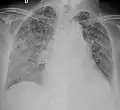

Miliary tuberculosis is a form of tuberculosis that is characterized by a wide dissemination into the human body and by the tiny size of the lesions (1–5 mm). Its name comes from a distinctive pattern seen on a chest radiograph of many tiny spots distributed throughout the lung fields with the appearance similar to millet seeds—thus the term "miliary" tuberculosis. Miliary TB may infect any number of organs, including the lungs, liver, and spleen.[2] Miliary tuberculosis is present in about 2% of all reported cases of tuberculosis and accounts for up to 20% of all extra-pulmonary tuberculosis cases.[3]

Tuberculosis of the lungs

Testing for miliary tuberculosis is conducted in a similar manner as for other forms of tuberculosis, although a number of tests must be conducted on a patient to confirm diagnosis.[4] Tests include chest x-ray, sputum culture, bronchoscopy, open lung biopsy, head CT/MRI, blood cultures, fundoscopy, and electrocardiography.[10] The tuberculosis (TB) blood test, also called an Interferon Gamma Release Assay or IGRA, is a way to diagnose latent TB. A variety of neurological complications have been noted in miliary tuberculosis patients—tuberculous meningitis and cerebral tuberculomas being the most frequent. However, a majority of patients improve following antituberculous treatment. Rarely lymphangitic spread of lung cancer could mimic miliary pattern of tuberculosis on regular chest X-ray. [15]

A case of miliary tuberculosis in an 82-year-old woman: